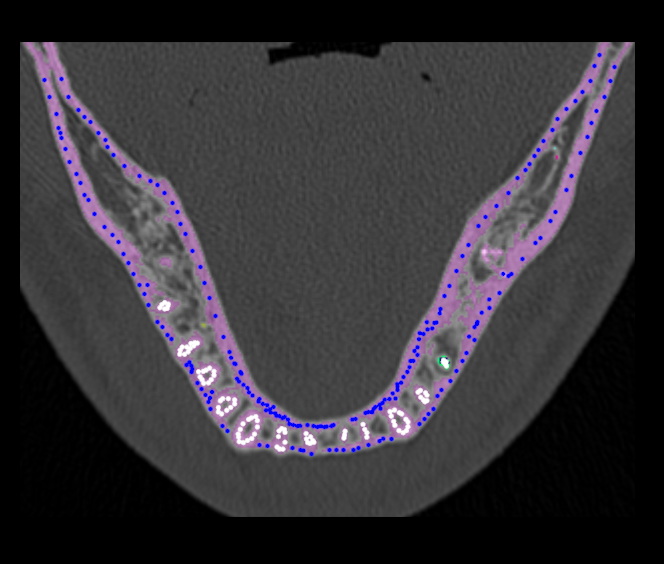

In this case, the result of the threshold transform will contain only the most optically dense part of pixels in the image of dental system: teeth and dense jawbone (Figure 2, the area colored pink).

Refer to caption

Figure 2: Result of the threshold transform and setting markers

Further, to select dentition from jawbone we use approach based on so-called morphological watershed transform with markers that often give more stable results of the image segmentation. Here we give only description of the approach. Justification and detailed exposition of the algorithm can be found in [7, 8].

Approach used to control excessive segmentation is based on the use of markers. Marker is a connected component belonging the image. We distinguish internal markers, belonging to the object of interest, and external markers, related to the background. In our case, the input image is the image obtained by threshold transform and containing jawboneand dentition only. Therefore, the object Dentiotion corresponds to the internal markers and the object Jaw matches the external markers. At that, setting of markers are carried out by user. Figure 2 illustrates set of markers on one slice of CT image.